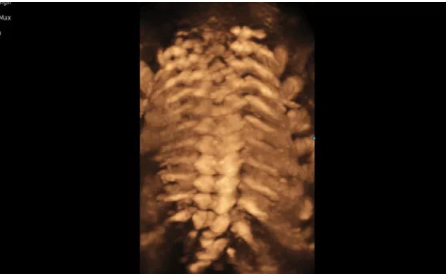

Hera i 10繼承并升級了全球首款5D超聲“三星麥迪遜WS80A”的“晶體結構”成像理念,即將CrystalBeam?波束形成技術、CrystalLive?超聲成像引擎、S-Vue Transducer?視覺傳感器集于一身,提供更清晰的圖像。

3D/4D成像方面,Hera i 10通過結合先進的圖像渲染技術,著重加強了邊緣和小結構的可視化能力。